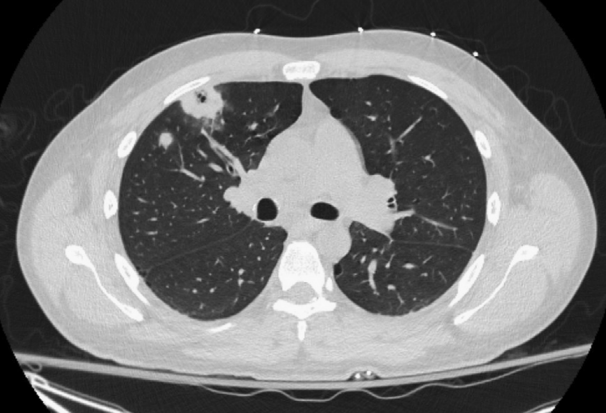

颈部增强CT扫描显示多发龋齿和左侧腭扁桃体肿大,并伴有周围炎性改变(图1)。胸部CT扫描显示双侧多发实性肺结节

图2 胸部CT扫描显示右上叶有空洞性病变